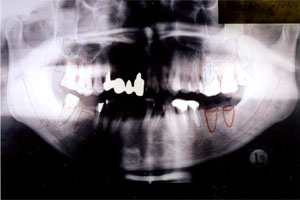

Xレイ オルソパントモグラフィー トリートメントプラン |

EXT抜歯 |

RCT・根菅治療 |

メタルクラウン |

MBセラミック・クラウン |

インプラント | |